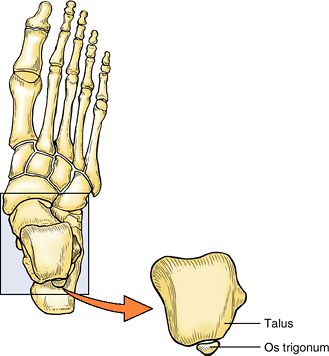

ossification center, which becomes the lateral tubercle of the talus,

occasionally fails to unite with the body of the talus. This failure

may be caused by applied stress (forceful plantarflexion) during the

early teens. Occasionally, a partly or even fully ossified center may

fracture and progress to non-union. Either event may result in a bone

(accessory ossicle) known as an os trigonum, which occurs in 14–25% of adults, more commonly bilaterally (Fig. B5.7).

It has an increased prevalence among soccer players and ballet dancers.

Patients with an os trigonum may be symptomatic or pain free.

Radionuclide bone scanning, which provides physiological as well as

anatomical evidence, is useful in distinguishing symptomatic and

asymptomatic ossicles. (Lawson, 1994)

Figure B5.7